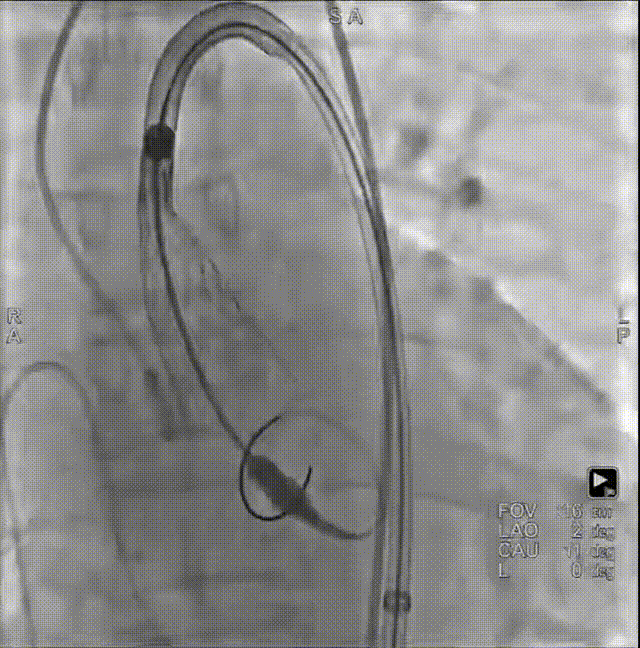

修建成教授 南方医科大学南方医院(点击查看专家详细简历) 细微之处防未然,创新携手寸寸安: 愈知临床无小事,任何风险的蛛丝马迹,都可能牵动全局。我常对团队说,真正的严谨,是将所有潜在 scenario 视作必然,在术前便一一拆解、化解 —— 如同在堤坝溃决前便筑牢每一寸基石,让风险连萌芽的机会都没有。 此次应用全球首创的预装干瓣,是基于对患者的综合考量,拥抱创新,实践创新,让创新携手助力“万全之策”的重要环节。 术前推演需要结合器械的特性:深度了解才能得心应手,结合患者基础病的相互影响并落实到术后 72 小时的并发症预警,每个环节都要像精密齿轮般咬合无误。这份 “穷尽万一” 的准备,从来不是对完美的苛求,看似耗时费力,实则是对生命最质朴的承诺 ——以医者的周全,携手创新的产品,为患者的万无一失不断努力! 患者病史 因 "反复胸闷伴活动后呼吸困难 3 年" 入院:患者 3 年前无明显诱因反复出现胸闷,部位在前胸,有憋气感,间有心悸,伴有活动后呼吸困难;外院就诊,查心脏彩超示 "主动脉狭窄、二尖瓣关闭不全"; 既往有高血压 20 余年,长期服用氨氯地平阿托伐他汀钙片降压治疗;有糖尿病 1 年,长期服用二甲双胍、阿卡波糖降糖治疗。 术前超声提示:主动脉瓣增厚、钙化并狭窄(重度)及关闭不全(轻度) 术前超声提示:主动脉瓣增厚、钙化并狭窄(重度)及关闭不全(轻度) 术前CT Type1型(R-N)二叶瓣,中度钙化集中在左窦瓣叶边缘及右无交界处,主动脉根部直径21.6mm,LVOT直径22.2mm,瓣上限制逐渐增大;双侧冠脉开口高度可,瓣叶短,窦部宽度足够,双冠VTC空间>4mm,预估冠脉风险小。 左室腔小,室间隔膜部短,有一定PPI风险;外周双侧入路无明显迂曲,双侧髂外动脉存在散在钙化、股动脉直径大,右股低分叉,能够支持20F大鞘通过。 手术策略 推荐右侧股动脉为主入路,放置20F大鞘,左侧为辅助入路,常规穿刺;使用20球囊预扩,预装AV23瓣膜;左右重叠位:RAO 1° CAU 28° ;右窦居中位:LAO 22° CAU 0° ;左冠切线回调:LAO 35° CRA 17° ;心室小,术前术中积极补液调整容量,做好循环崩溃处理准备。 手术过程 主动脉根部造影 20mm球囊预扩 - 无腰无漏 瓣膜初始定位 工作位观察瓣膜 - 冠脉通畅,位置合适 最终造影观察 - 无瓣周漏、挂钩处于最右方-Commisural Alignment 术前压差120mmHg,术后压差2mmHg。 Prostyle A®预装干瓣——助力临床最优化解决方案: 平衡的径向支撑力:该病例为TYPE 1型二叶瓣,对产品的径向支撑力是一种考验,术后影像彰显Prostyle A®综合设计带来平衡的径向支撑力,轻松应对高钙化病变,符合中国国情,为二叶瓣患者带来信心保障; 轻松过弓,精准可控:该病例主动脉弓角度可,但弓距小,考验产品的通过性能,术中顺利过弓,未使用snare轻松过弓; 预装干瓣 便捷顺安:金仕生物专利抗钙化技术运用纳米技术去除组织内的细胞碎片和磷脂,封闭游离醛基,从根本上阻断了瓣膜钙化的多项因素,显著提升了瓣膜的耐久性;同时,相比较传统戊二醛保存方式,干式存储最大限度的保留心包的亲水亲油平衡,还原组织天然曲柔性,进一步保障了瓣叶开合,保证长期耐久性。